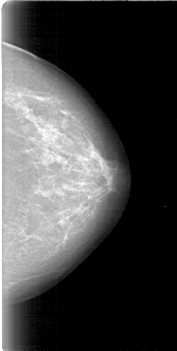

D_4011_1.RIGHT_MLO

D_4011_1.LEFT_MLO

D_4011_1.RIGHT_CC

D_4011_1.LEFT_CC

LEFT_CC LINES 5251 PIXELS_PER_LINE 2641 BITS_PER_PIXEL 12 RESOLUTION 43.5 NON_OVERLAY

LEFT_MLO LINES 5386 PIXELS_PER_LINE 2851 BITS_PER_PIXEL 12 RESOLUTION 43.5 NON_OVERLAY

RIGHT_CC LINES 5296 PIXELS_PER_LINE 2236 BITS_PER_PIXEL 12 RESOLUTION 43.5 OVERLAY

RIGHT_MLO LINES 5311 PIXELS_PER_LINE 2521 BITS_PER_PIXEL 12 RESOLUTION 43.5 OVERLAY

LESION_TYPE MASS SHAPE OVAL MARGINS OBSCURED

ASSESSMENT 0

SUBTLETY 4

PATHOLOGY BENIGN